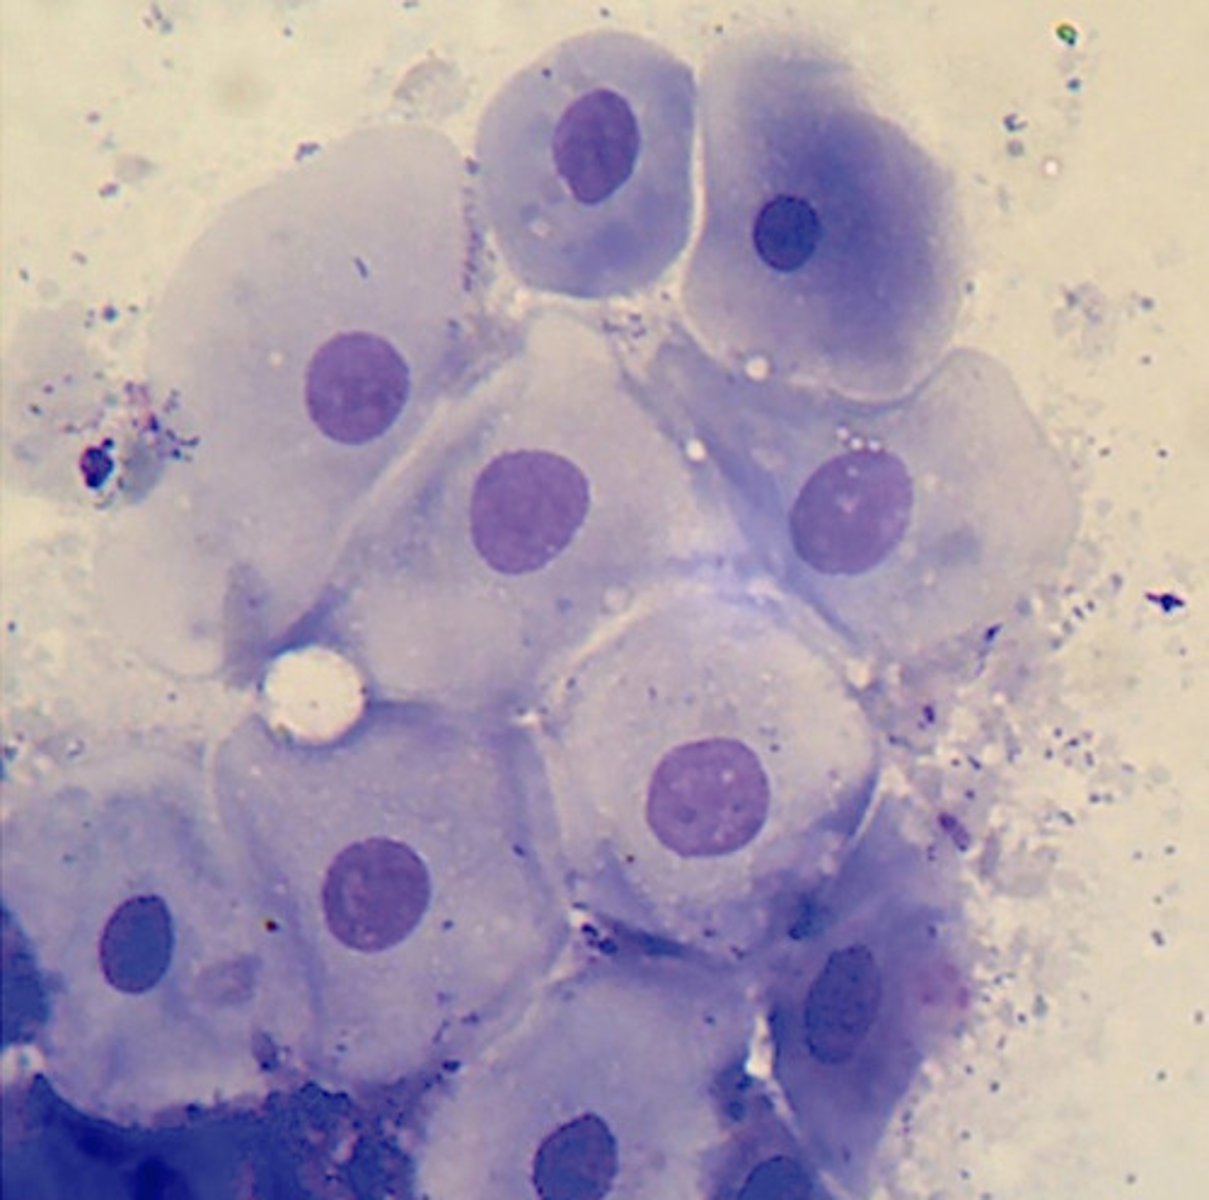

parabasal cell

vaginal cytology

round shaped and stippled nucleus

intermediate cells

vaginal cytology

angular shape and stipples nucleus

superficial cells

vaginal cytology

angular shape and pyknotic nucleus